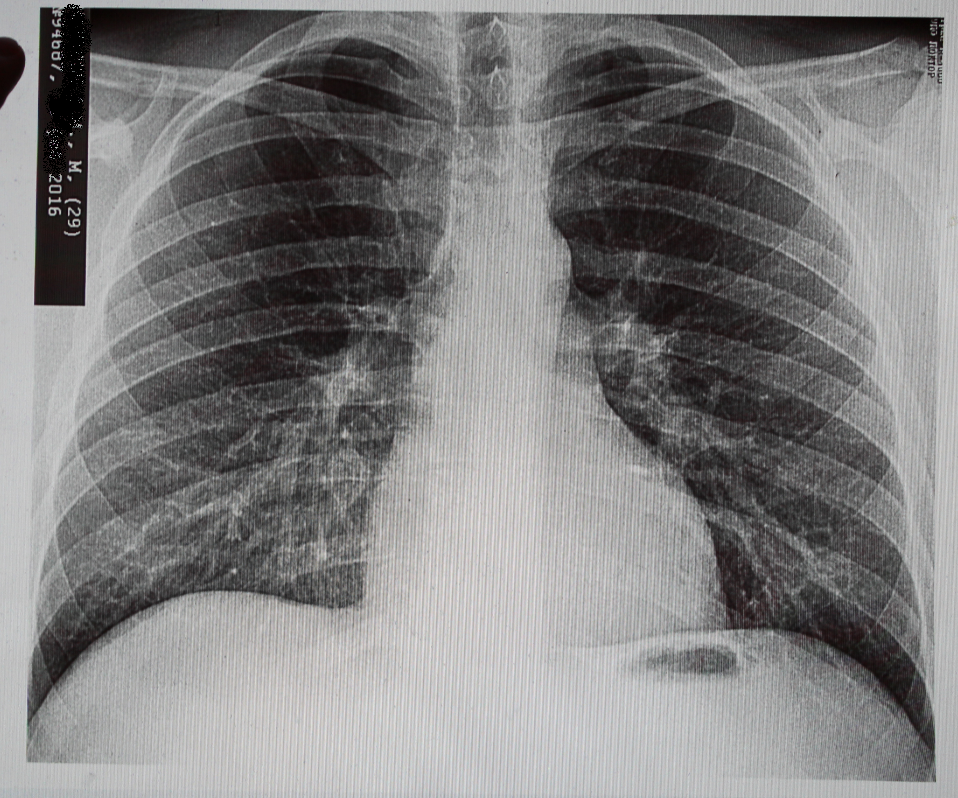

Нормальная рентгенограмма легких: что нужно знать

Раздел: Мудрость в объективе